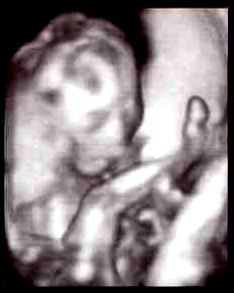

では今回の4D画像をどうぞ。

実際はこんなにデコボコしてる訳じゃないですよー。

多分、シャッターのタイミングで画像がぶれるのかと。

パグ夫くんはこれを見て

「きれいな顔してる!!」

って。

既に親バカ(笑)